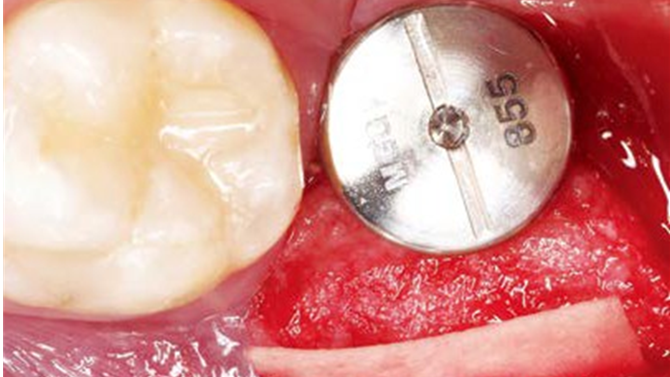

“AnyRidge implant enables fast and stable

osseointegration at this extreme case of bone defect. ”

Clinical case: Bone filling into the bottom of deepest thread at 8.0mm AnyRidge fixture

- Courtesy of Dr. Kwang Bum Park -

Keywords

AnyRidge, Knifethread ,extraction socket, ,initial stability ,Allograft, ,osseointegratio ,Dr. Kwang Bum Park, , Mandibular, Single replacement, AnyRidge, Mega-oss,

Products used

Implant system-AnyRidge, Regeneration-Mega-Oss

How can primary stability be increased?

Primary stability is especially important in the case of poor quality bone. The instability of dental implants results in fibrous encapsulation and failed osseointegration (Lioubavina-Hack, et al. 2006). One method for increasing primary stability is modifying the surgical technique for implant placement. Studies have reported that the undersized surgical technique, which uses a final drill diameter smaller than the diameter of the implant, results in a higher primary stability when compared with the press-fit technique (Tabassum, et al. 2009, Tabassum, et al. 2010a).

Ti implants with a deeper thread depth provide a higher surface area, which is advantageous for increasing stability in areas of poor quality bone (Abuhussein, et al. 2010). Ti implants with deeper thread depths also facilitate an increased load and mechanical interlocking with poor quality bone.

Another method increasing the primary stability is to change the implant design, such as the shape of the implant body and thread, length, and diameter. Various thread designs for taper implants and other dental implant designs have already been reported to effect the primary stability. Taper implants also show a higher primary stability than cylindrical implants (Kim, et al. 2009, Sakoh, et al. 2006, Wilmes, et al. 2008).

Meanwhile, dental implants with a long length or wide diameter show a significantly increased insertion torque (Kim,et al. 2009, Wilmes, et al. 2008). Plus, dental implants without self-tapping blades have a higher primary stability than implants with self-tapping blades (Kim et al. 2011).